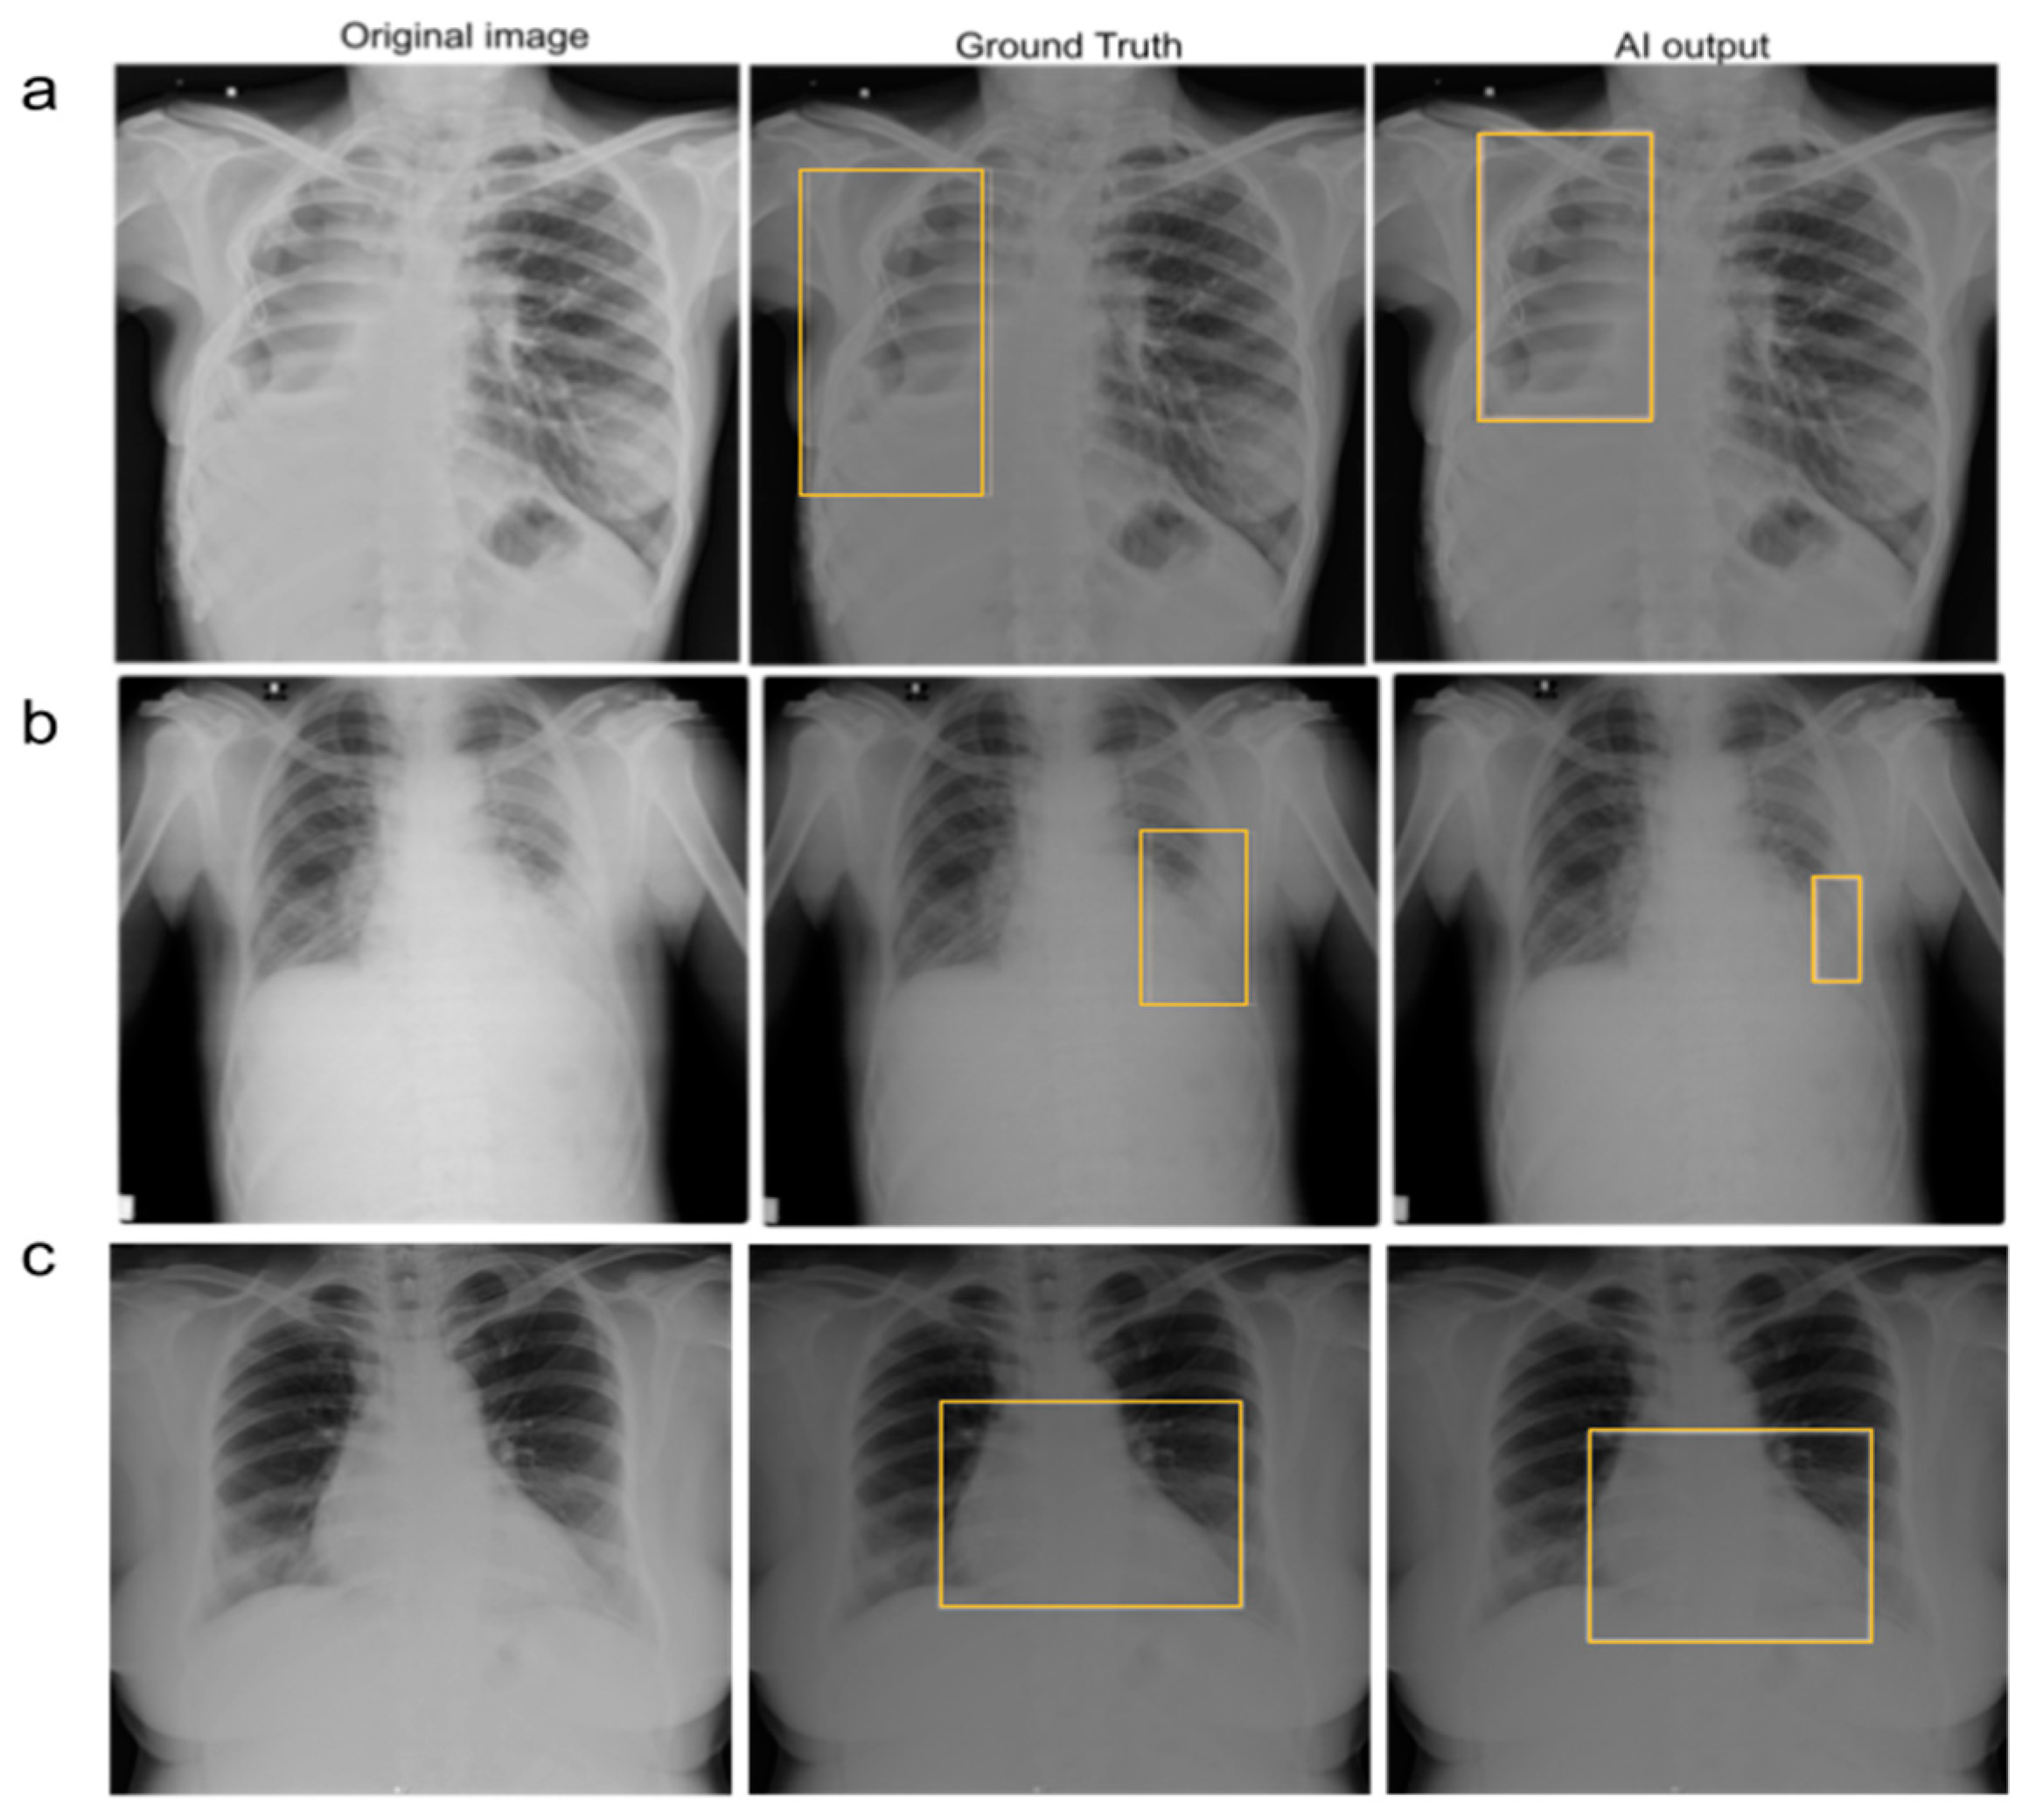

2.2. Establishing Ground Truth

2.3. AI Model